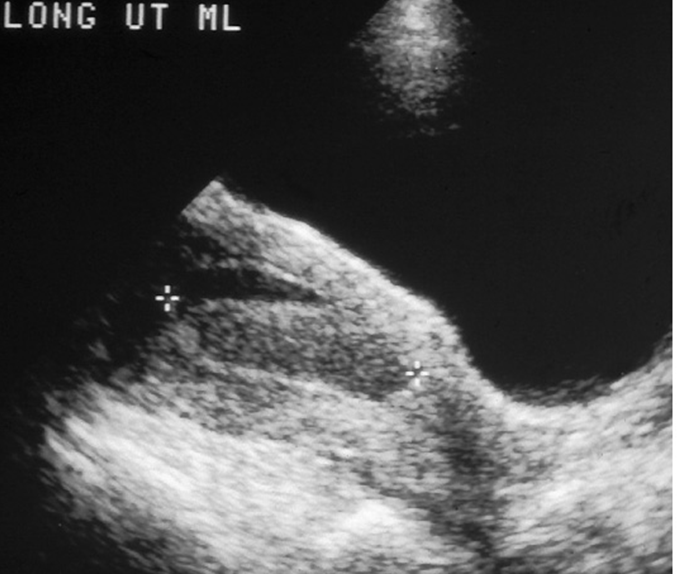

Long-axis Outflow Tract/ LVOT

What view is this?

LVOT / Long axis